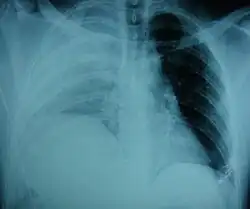

| .jpg) | |

| An X-ray showing a raised diaphragm on the right[1] | |

Physical examinations are not accurate, as there is usually no specific physical sign that can be used to diagnose this condition.[3] Thoracoscopic and laparoscopic methods can be accurate.[12] Chest X-ray is known to be unreliable in diagnosing diaphragmatic rupture;[4] it has low sensitivity and specificity for the injury.[5] Often another injury such as pulmonary contusion masks the injury on the X-ray film.[6] Half the time, initial X-rays are normal; in most of those that are not, hemothorax or pneumothorax is present.[4] A nasogastric tube from the stomach may appear on the film in the chest cavity; this sign is pathognomonic for diaphragmatic rupture, but it is rare.[4] The X-ray is better able to detect the injury when taken from the back with the person upright, but this is not usually possible because the person is usually not stable enough; thus it is usually taken from the front with the person lying supine.[5] Positive pressure ventilation helps keep the abdominal organs from herniating into the chest cavity, but this also can prevent the injury from being discovered on an X-ray.[4]